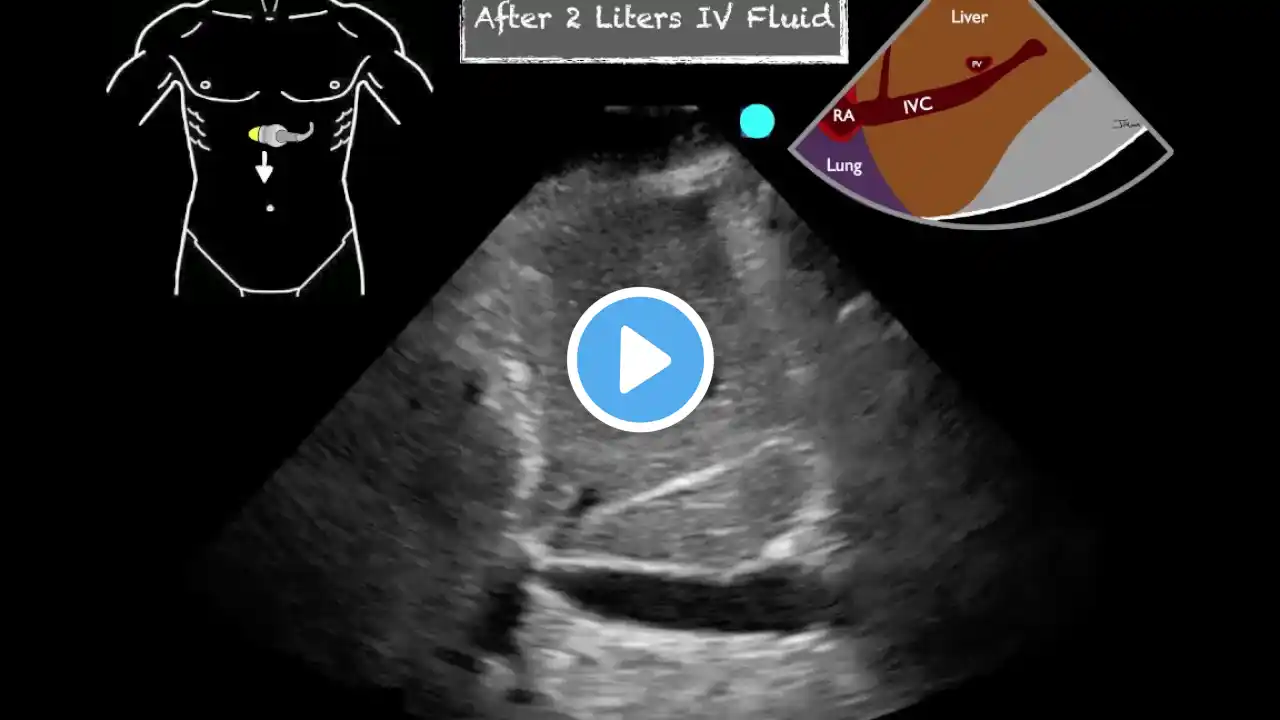

In this lecture from our Ultrasound Grand Rounds, Dr. Matthew Tabbut, MD talks using the IVC to assess volume status in the emergency department. --- Follow us on Online and on Social Media: ✅ Website: https://www.metrohealth.org/pocus ✅ Twitter:   / mh_emultrasound   ✅ Instagram:   / mh_emultrasound   --- This is the official account of the Case Western Reserve University & MetroHealth Medical Center Emergency Medicine Ultrasound Division. Videos are not medical advice or views/policy of these institutions.